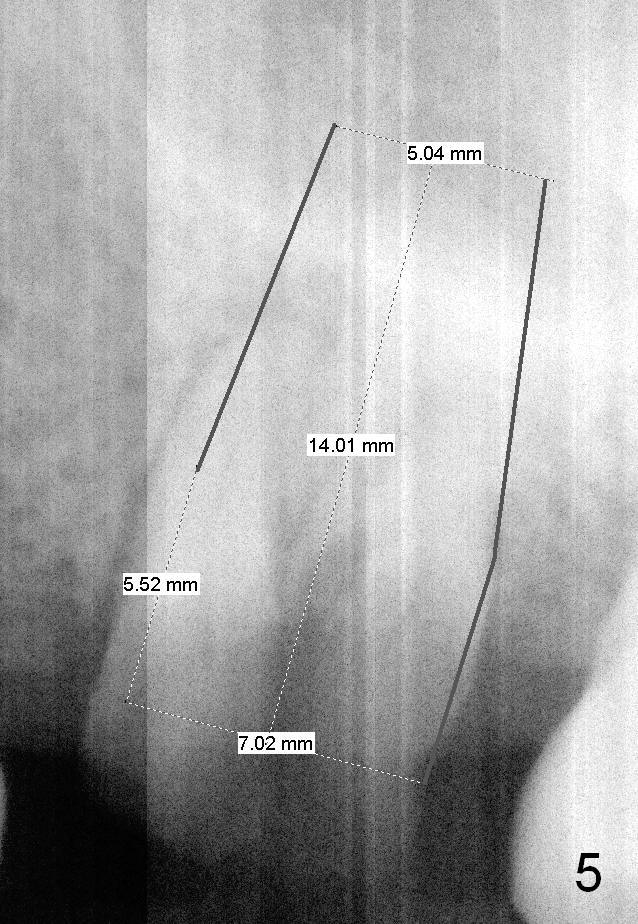

A 49-year-old man requests to restore #14 with residual roots (Fig.1). There is periapical radiolucency (Fig.2 *). A 5.9x10 mm bone-level implant is placed with minor sinus lift (Fig.3), whereas a short (Fig.4) or long (Fig.5) tissue-level implant is placed without or with sinus lift. The implant could be as large as 7 mm (Fig.5) to prevent post-extraction ridge atrophy.

To place an implant in the center of the septum, the smallest pilot drill will be used for 6 mm. Insert a parallel pin with millimeter marks and take the 1st intraop PA. Change the trajectory if necessary. Combination of reamers and osteotomes will be used to enlarge the osteotomy, followed by taps and an implant.